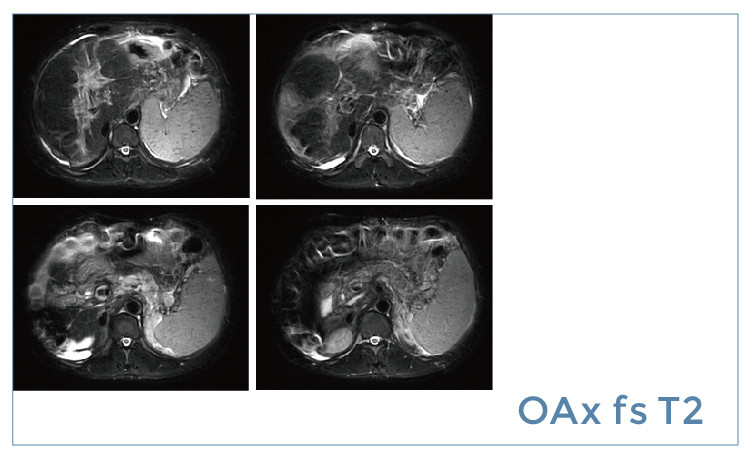

【朗润影像档案】20190614磁共振影像病例结果讨论

【朗润影像档案】磁共振影像病例分享(编号20190614)